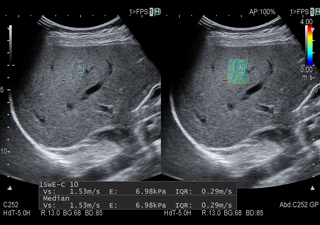

プローブからプッシュパルスを送信し、組織をひずませます。ひずんだ組織が元の位置に戻ろうとするときにせん断波(Shear Wave)が発生します。ある特定の2点それぞれにせん断波が到達した時間を検出し、到達時間の差(time lag)と2点間の距離(distance)からせん断波の伝搬速度(Vs)を計測し数値化します。

1回の計測でm個の点に対し、n回のパルスを送信することでm×n個のVsを計測します。その中で有効とされる値の中央値をVs値として算出します。

信頼性指標(VsN)は、1回の測定で得られた複数個のVs値の集合から、有効な値の割合をVsNとして表示します。この機能により計測が妥当であったかどうかを評価できます。

せん断波(Shear Wave)の伝搬速度をもとに、組織の硬さを色付け表示します。さらにROI内の任意の箇所の硬さを数値化することで、定量評価が可能となります。肝線維化の程度を視覚的かつ非侵襲的に評価できます。